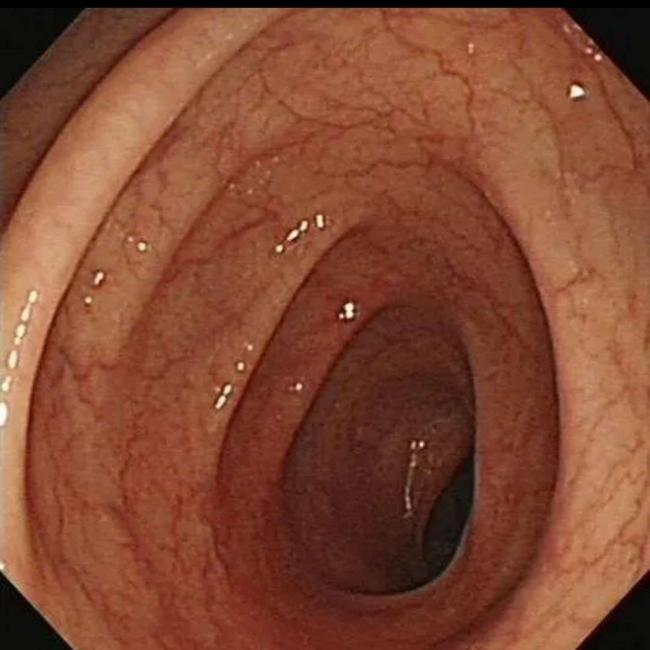

临床上许多患者自行口服药物后筛查肠镜,均有不同程度的结肠黑变病。正常的结肠黏膜是淡红色的,看起来光滑平坦,黏膜表面的小血管纹理清晰可见。而结肠黑变病的肠黏膜色泽呈现棕色、褐色,有豹纹或者蛇皮一样的条状纹,严重的甚至会变成黑色。